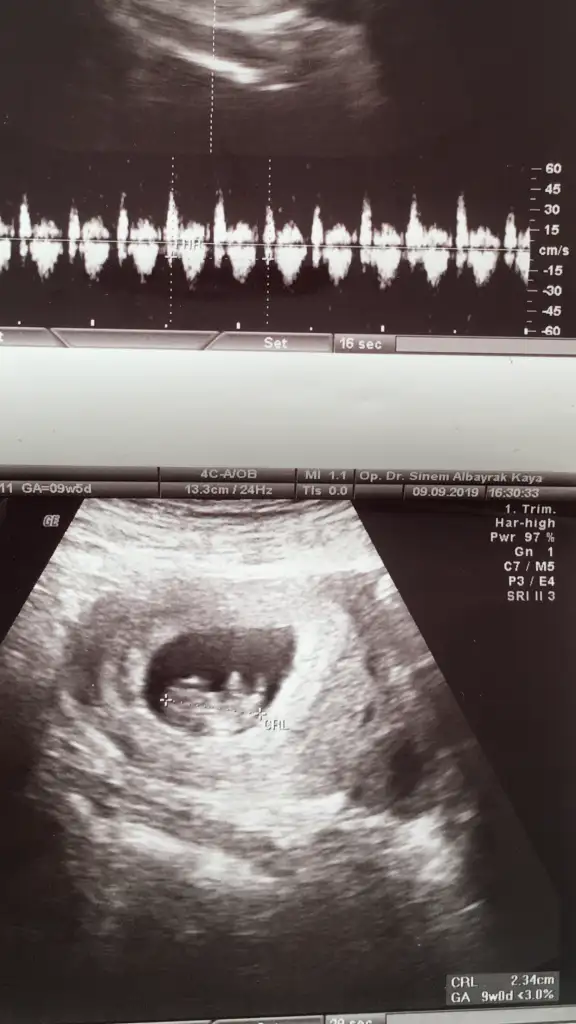

merhaba 9 haftaligiz.erkek gibi geldi bana.kizlar kendini gizler diye okumustum burada.sizin fikriniz nedir

• 8D0BD885-1ABE-4119-9FC7-B69988433E52.webp

8D0BD885-1ABE-4119-9FC7-B69988433E52.webp

30,8 KB · Görüntüleme: 60